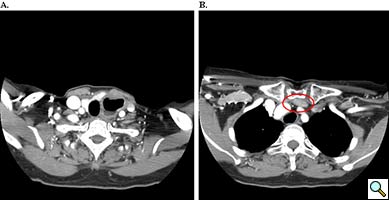

A 67 year old patient with a history of transhiatal esophagectomy (THE) and sub-sternal gastric pull-up ten years prior, at another institution, for early stage esophageal cancer presented with progressive dysphagia to solids. An initial esophagogastroduodenoscopy (EGD) found a large retained food bolus as well as tortuosity and dilatation of the cervical esophagus proximal to the esophagogastric anastomosis. No evidence of intrinsic anastomotic stricture or fibrosis was noted, but there was extrinsic compression. A barium esophagogram revealed significant extrinsic compression of the upper esophagus in the area of the anastomosis at the left clavicular head, with associated narrowing of the lumen and minimal transit of oral contrast (Figure 1). A computed tomography scan of the neck confirmed the sub-sternal location of the gastric pull-up within the anterior mediastinum, and revealed dilatation of the esophagus proximal to the anastomosis, with no associated masses or disease recurrence (Figure 2). The left sternoclavicular joint (SCJ) appeared to be compressing the conduit and was the point of obstruction.